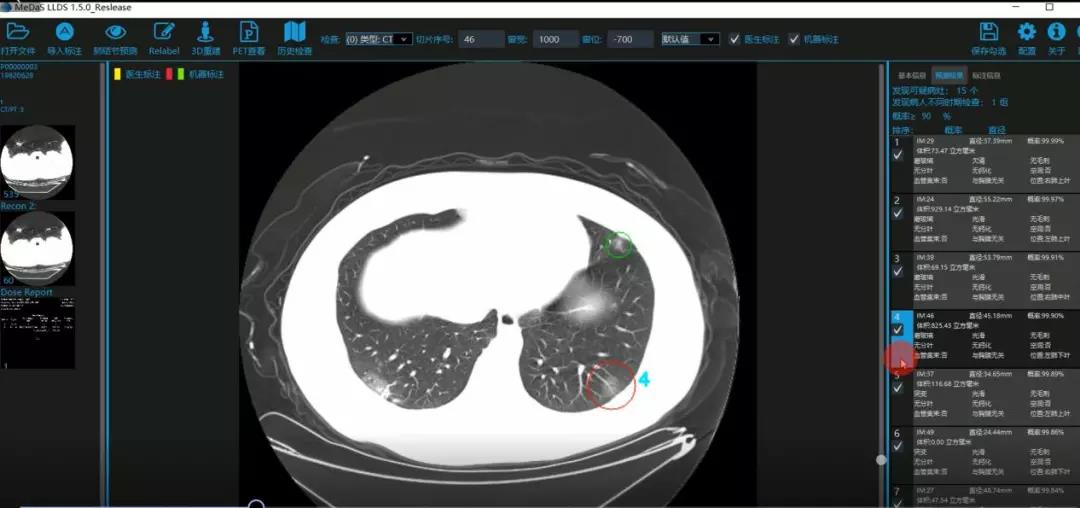

医护人员的好帮手:基于深度学习的新冠肺炎早期检测筛查系统

西电beat365亚洲体育官方网站智能软件与系统新技术研究所副教授张亮的爱人是西安交通大学第二附属医院抗疫一线的影像科医生,疫情发生以来,他们讨论最多的就是新型冠状病毒感染者的早期诊断问题。作为一名医护家属,身为高校科研工作者,张亮深知快速准确地诊断新冠肺炎早期患者对控制和防治疫情的重要性和挑战性。他与团队成员主动出击,通过远程网络会议,在前期医学影像处理的研究基础上加速科研攻关,反复讨论方案,屡次设计模型,与上海宽带技术及应用工程研究中心、上海交通大学医学院附属瑞金医院等合作单位的人员多次标注整理患者肺部CT影像数据到深夜。与此同时,他们依托上海瑞金医院、西安交通大学第二附属医院等的新冠肺炎疑似、确诊患者肺部CT影像,通过综合分析新冠肺炎患者的肺部CT影像特点(磨玻璃、体积大小、位置等特征),张亮团队加快技术攻关,设计开发了基于深度学习的新型冠状病毒的早期检测筛查模型系统。

对应新冠肺炎CT病灶检测效果

令人欣喜的是,通过对实际门诊数据排查测试,该模型可以减轻医护人员近80%的工作量,新冠肺炎患者的检测召回率超过95%。目前,模型系统正在进行最后的调试工作,很快投入到“战疫”一线,缓解医护人员紧缺、确诊检测工作耗时较长等问题,减少医护人员的工作时间和劳动强度,提高工作效率。